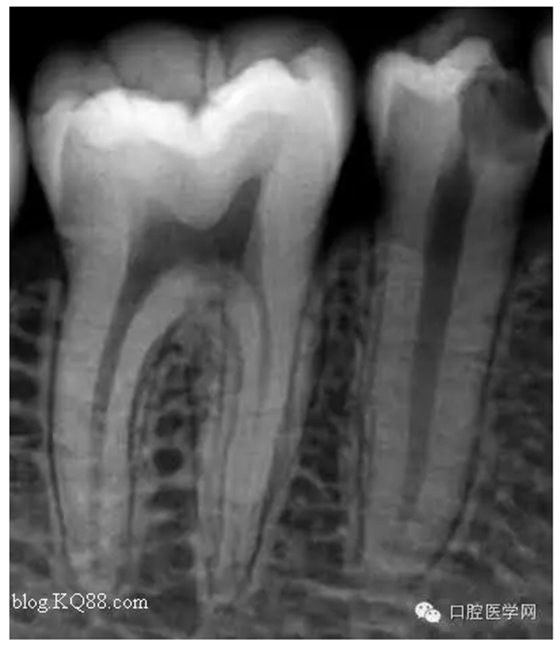

病人是我的助手,牙齒酸痛一周。吃冷熱時加重。無自發(fā)痛。先看看牙片

根據(jù)主訴:一過性冷熱痛無自發(fā)痛,X線:根尖無明顯改變應(yīng)診斷為深齲。小伙子平時愛吃冷飲最近冷飲是不敢吃了。